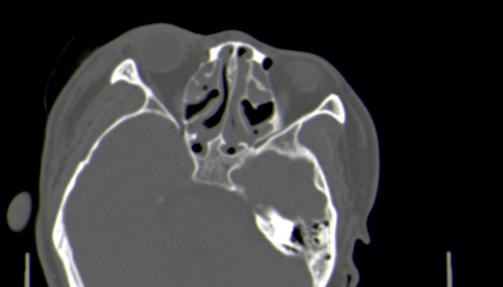

以下是引用皎皎白驹在2006-11-29 8:48:00的发言:[br]影像表现:双侧筛窦和上颌窦、鼻腔内均密度增高,右侧视神经增粗、弯曲,左筛窦顶部筛板及右侧纸板近视神经孔区可见骨折线。[br]结合临床表现考虑:右侧筛窦纸板近视神经孔区骨折致右侧视神经损伤。最好做个眼眶冠状扫描,更明确右侧视神经管是否狭窄。

以下是引用w_jianhua在2006-11-29 10:07:00的发言:[br]影像表现:双侧筛窦和上颌窦、鼻腔内均密度增高,右侧视神经增粗、弯曲,左筛窦顶部筛板及右侧纸板近视神经孔区可见骨折线。[br]结合临床表现考虑:右侧筛窦纸板近视神经孔区骨折致右侧视神经损伤。最好做个眼眶冠状扫描,更明确右侧视神经管是否狭窄。 [br] [br]支持[br]

以下是引用守望可可西里在2006-11-29 9:46:00的发言:[br][quote]以下是引用皎皎白驹在2006-11-29 8:48:00的发言:[br]影像表现:双侧筛窦和上颌窦、鼻腔内均密度增高,右侧视神经增粗、弯曲,左筛窦顶部筛板及右侧纸板近视神经孔区可见骨折线。[br]结合临床表现考虑:右侧筛窦纸板近视神经孔区骨折致右侧视神经损伤。最好做个眼眶冠状扫描,更明确右侧视神经管是否狭窄。